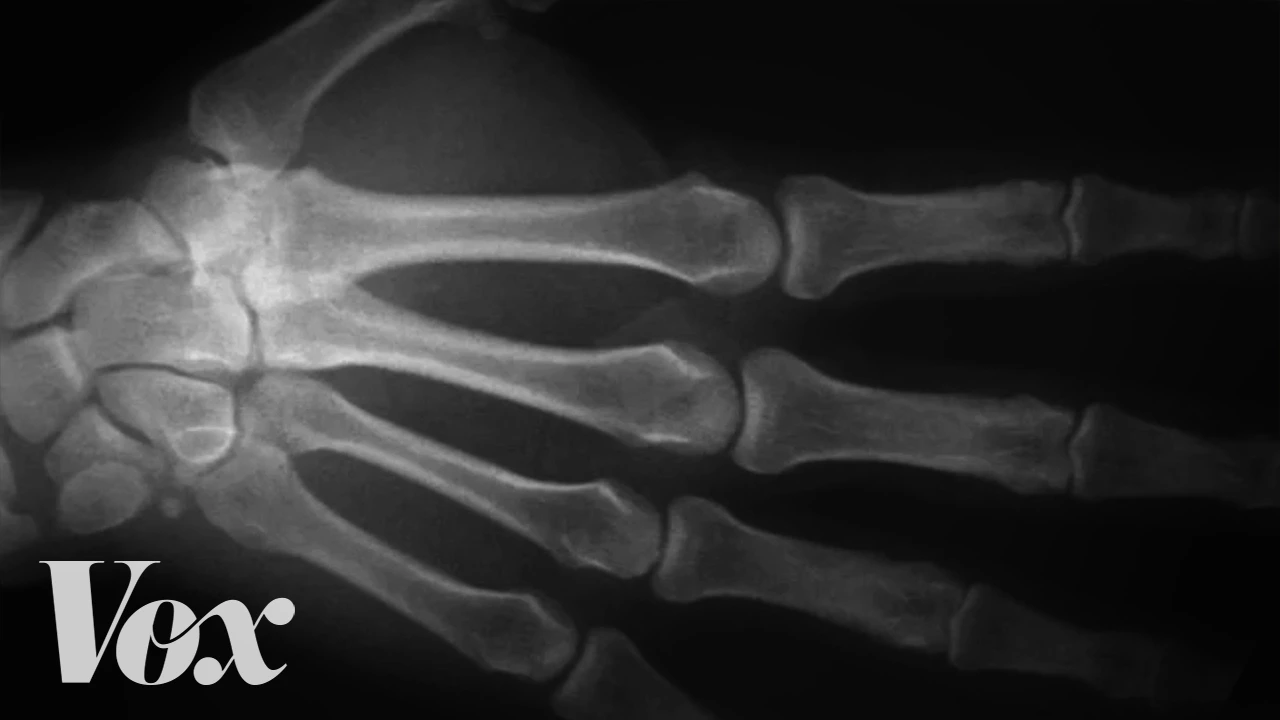

And is it bad for you? Synovial fluid is this lubricant-like substance that's found in between your joints. It kind of looks like an egg yolk.

So when you stretch out your joint, you are releasing gas, and that gas forms a bubble and it collapses and pops. In order to crack the same knuckle again, you have to wait about 20 minutes for the gas to return back to that fluid. So how is that different from a pop you hear when you stand up quickly?